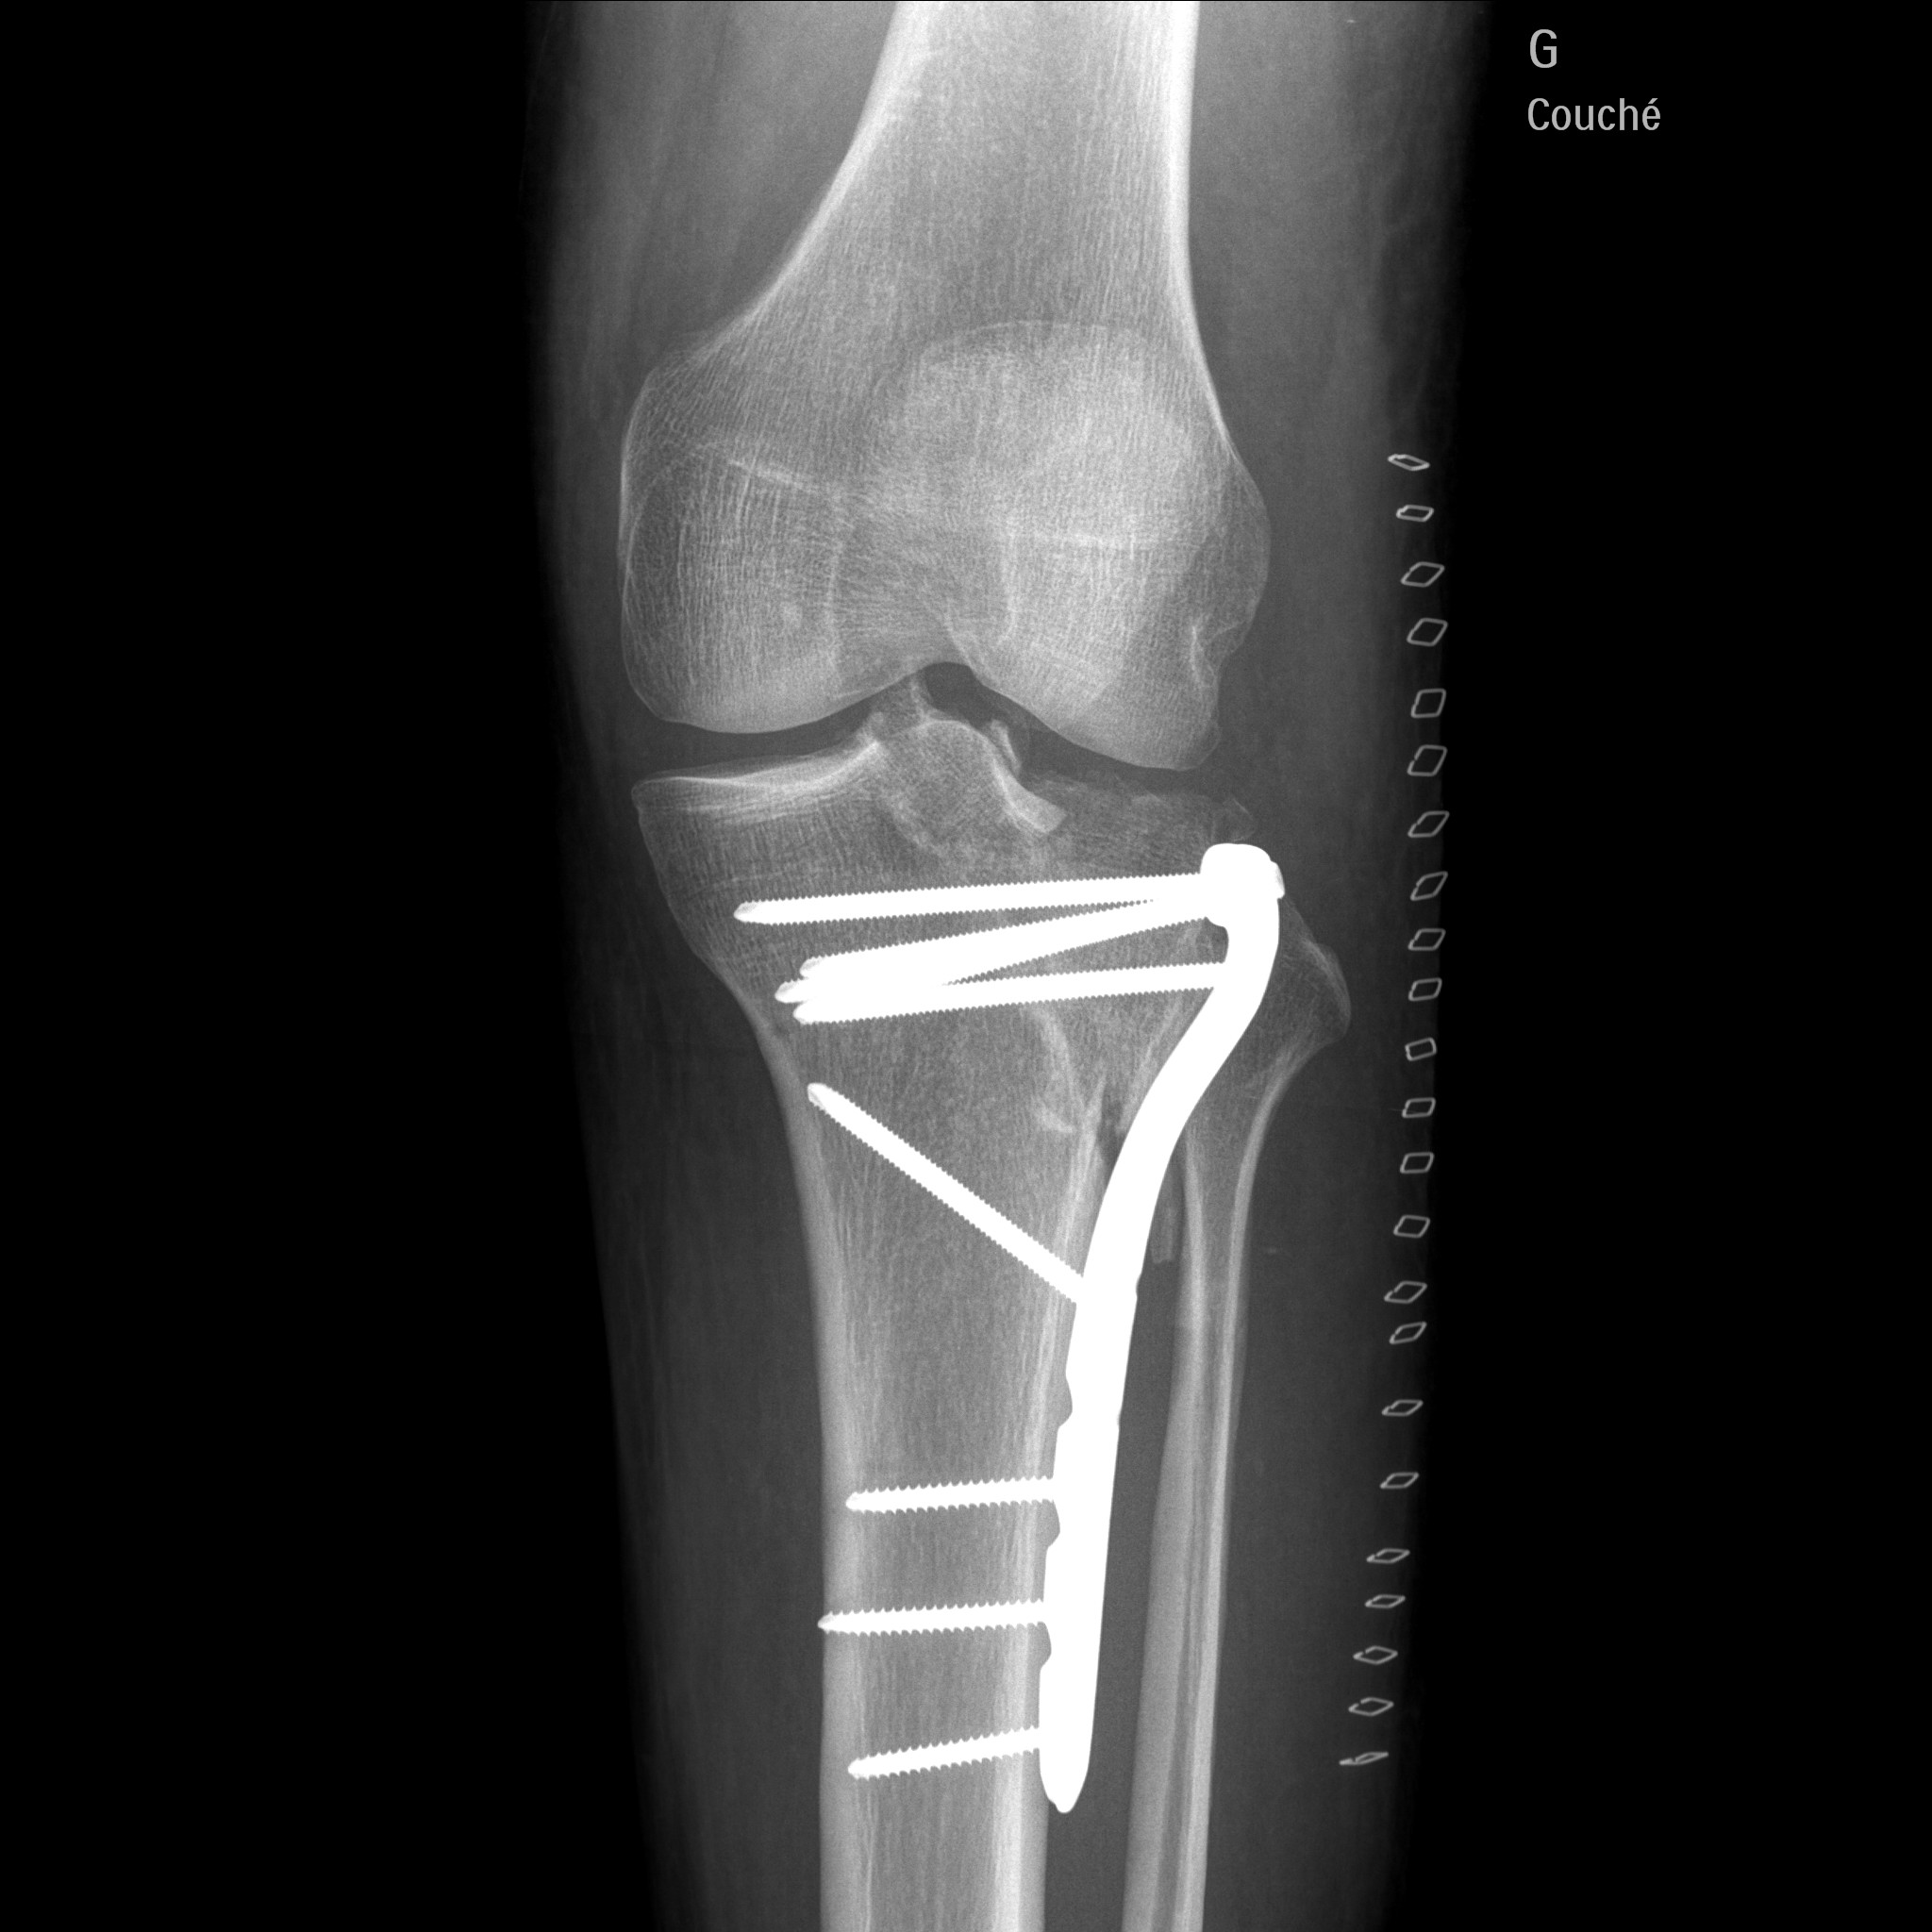

j'ai fait une sale chute en moto et j'ai du me faire opéré :( :( :( :(

j'en ai pour 3 mois sans pauser le pied a terre , et 6 mois de rééducation 1 an pour récupéré la totalité de ma jambes

1.3.46.670589.30.39.0.1.622692733605.1619697890621.1-f1.jpeg

1.3.46.670589.30.39.0.1.622692733605.1619697890648.1-f1.jpeg

Tu as dû avoir la trouille de ta vie. Un peu plus haut c'était toute l'articulation qui prenait.

Ouaouuu....ah oui c est du lourd la. Beau travail de chirurgie...a la hauteur de ce que tu sais faire de ton cote :wink: